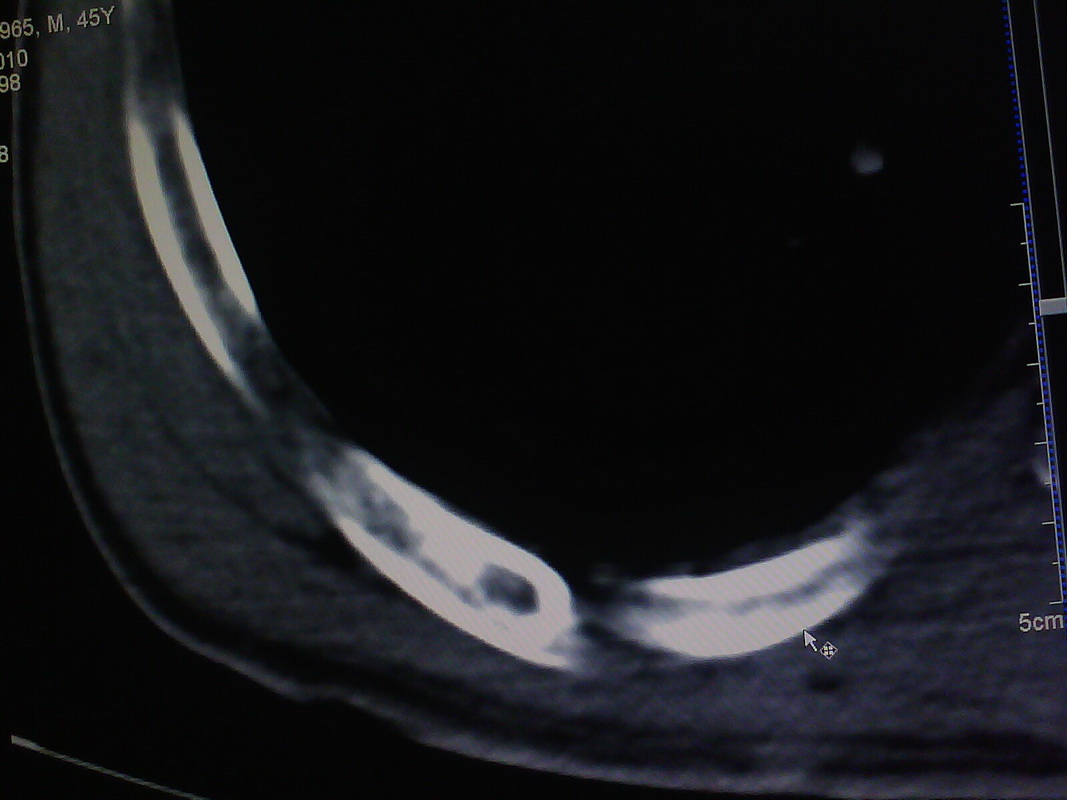

患者,男性,41y,外伤病号,来拍片,发现右侧第9后肋,肋骨膨大,有密度不均,想问大家,是否有问题,要考虑什么东西,谢谢

右侧第九后肋骨纤维结构不良。

考虑骨纤维异常增殖症(混合型)。

肋骨是骨纤好发部位。